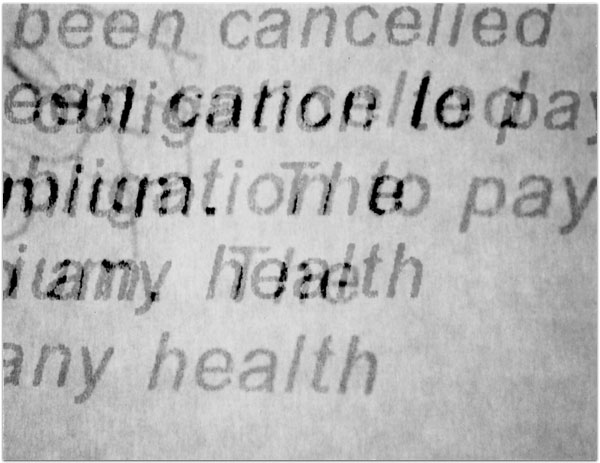

- Itis

- 2004

- 3.25″ × 4.25″

- Photographic montages of my hands & health paraphernalia on Polaroid Type 664 & 669 Film using a Daylab Printer.

- Frustrated by a lack of mobility and severe pain with my fingers, unable to accomplish any task requiring joint dexterity,

I noticed piles of health related papers strewn around. I layered these in a slide printer without removing

my hands, enlarging both onto the film.